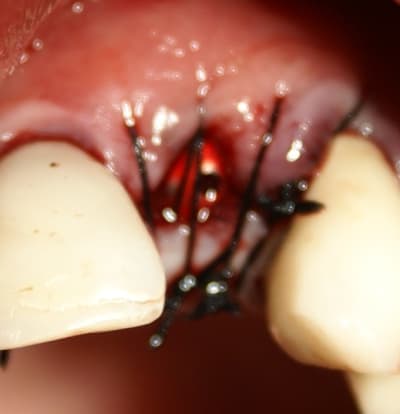

Bien vu! cela demande une petite explication.

j'ai d'abord enfoui le plus apicalement possible ma membrane car je devais en premier lieu combler avec le moignon en place de manière à ne pas mettre de substitut osseux dans l'hexagone interne. Une fois mon substitut en place je travail le porte implant qui sert de support à la provisoire, il y a donc montages et démontages successifs.

Comme tu l'as si bien remarqué, j'ai laissé une minuscule languette de membrane, je l'a tracte très légèrement (une fois seulement la provisoire validée et prête à poser) et la fixe en la transperçant avec le moignon portant la provisoire. ainsi je recouvre bien le substitut osseux en palatin et en vestibulaire également.

remarque:

Cette dernière opération est très délicate quand c'est une vis de cica car elle entraine la membrane en l'enroulant (ce qu'amibien décrit plus haut) .